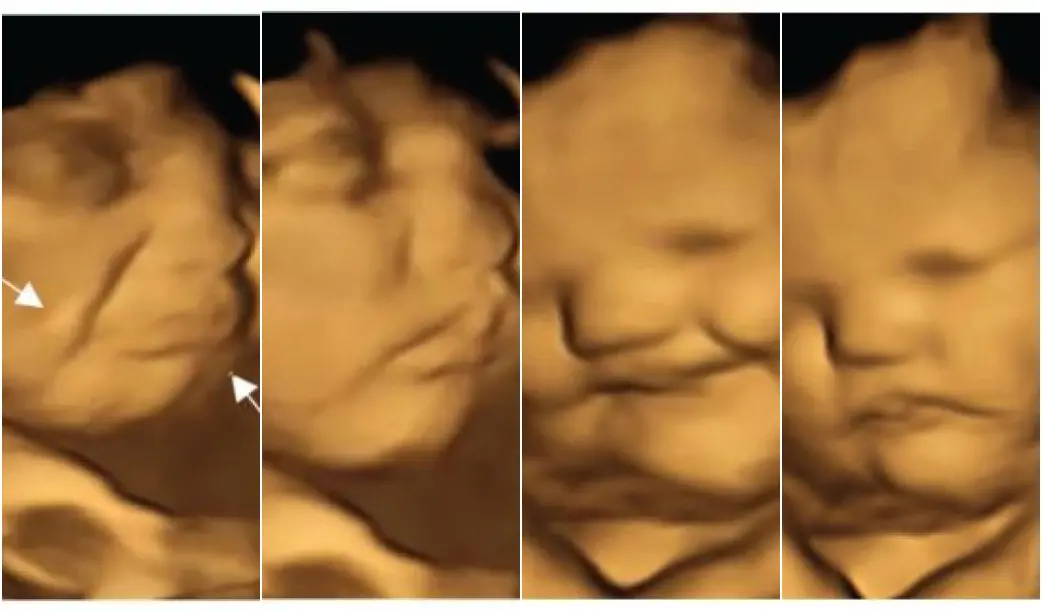

Legenda: Exames mostraram expressões dos fetos diante da alimentação das mães

Foto: Reprodução/Psychological Science

No estudo, realizado por pesquisadores da universidade britânica de Durham e da francesa de Borgonha, publicado nesta quinta-feira (22) na revista Psychological Science, foram realizados ultrassons 4D em 100 mulheres de 18 a 40 anos e gestantes de 32 a 36 semanas.

As imagens permitiram observar como os futuros bebês reagem quando as mães comem determinados alimentos. Diante da cenoura, os fetos exibiram um rosto sorridente, enquanto aqueles cuja mãe havia comido couve tinham cara de choro, afirmaram os cientistas.